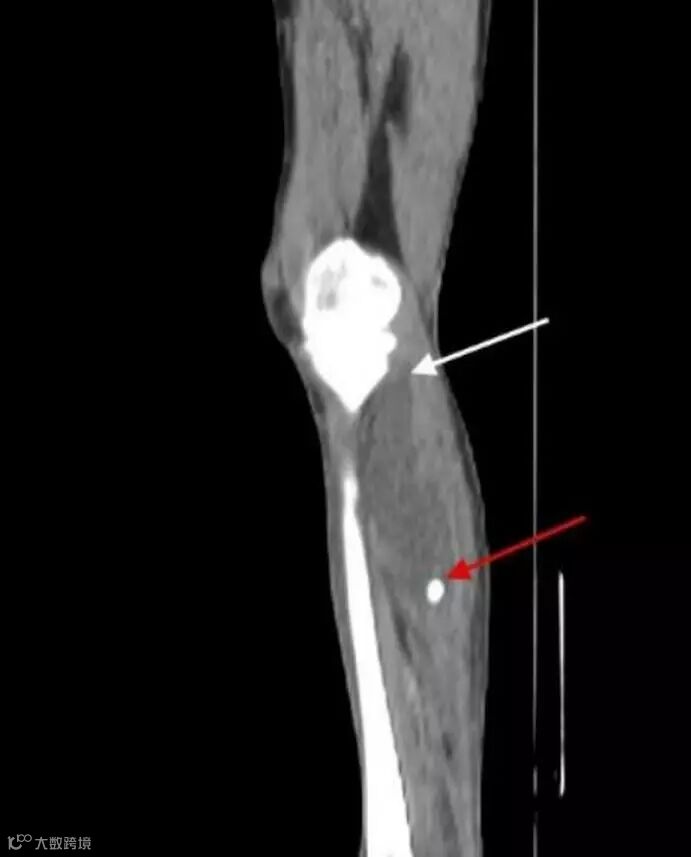

Sagittal reformatted CT image of the left lower extremity demonstrates a cystic structure originating posterior to the medial femoral condyle (white arrow) and extending into the calf soft tissues. There is a calcified body (red arrow) within the inferior aspect of the cyst.

Axial CT image at the level of the mid calf demonstrates a calcified body (red arrow) within a cystic structure deep to the medial head of the gastrocnemius muscle (white arrow).